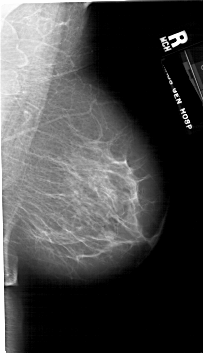

A_1760_1.RIGHT_MLO

RIGHT_MLO LINES 6691 PIXELS_PER_LINE 3856 BITS_PER_PIXEL 12 RESOLUTION 43.5 NON_OVERLAY